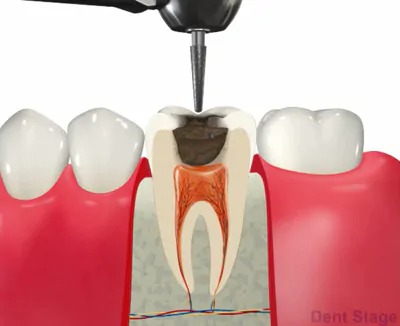

2むし歯除去

痛みの原因となっているむし歯を取り除きます。

3抜髄

炎症を起こしてしまった神経を抜いていきます。この時使用するのはファイルというヤスリのようなものを使用します。